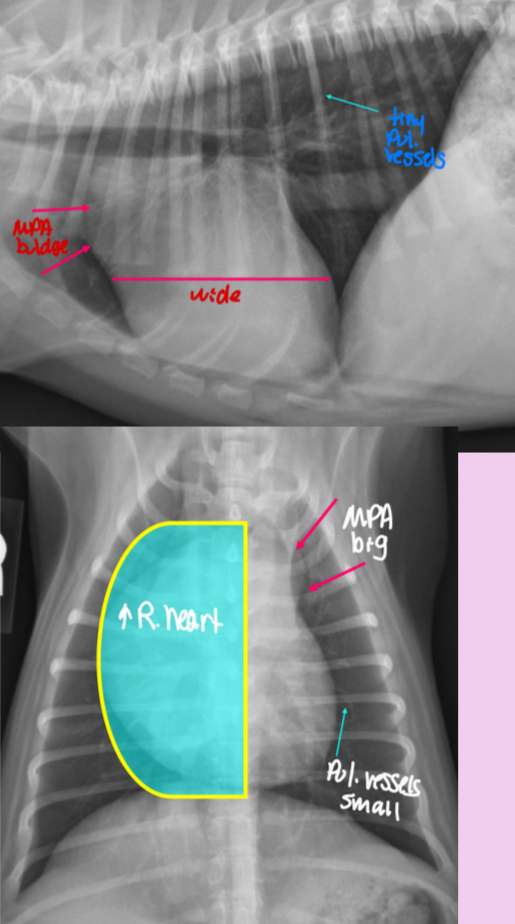

What part of the outflow tract is obstructed in aortic stenosis

Left ventricular outflow tract

Aortic stenosis happens at what level

-subvalvular/valvular

Subvalvular (subaortic stenosis)

What breed is aortic stenosis heritable in

Newfoundland dogs

Other breeds: Rottweilers, boxers, golden, GSD (large breeds)

Roentgen signs of aortic stenosis

-survey rads could be NORMAL

-LH enlargement (LVE ± LAE) from PRESSURE OVERLOAD

-elongated cardiac silhouette

-AA bump

-low incidence of LHF

What ends up killing the dogs with aortic stenosis

Sudden death due to ventricular arrhythmias and impaired coronary arteries

Pathogenesis of aortic stenosis

1.subaortic abnormality

2.left ventricular hypertrophy

3.focal dilation of AA

What does the angiocardiography highlight in aortic stenosis

-AA bulge

-increased cardiac waist

-left ventricular hypertrophy

-narrowing of aortic outflow tract

-post stenotic dilation of AA

± mitral regurg

What disease does this dog have

Aortic stenosis